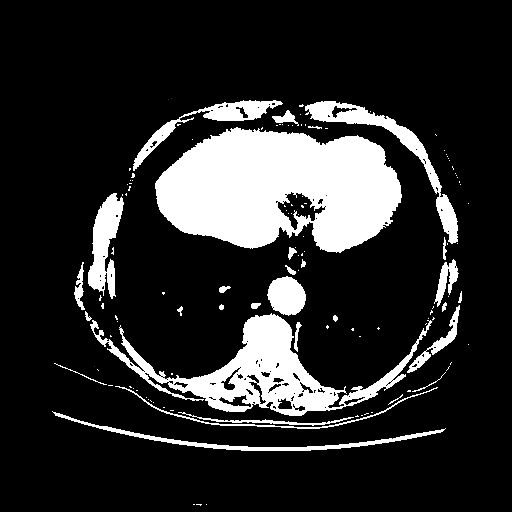

Slice 70 Targeting Evaluation

Patient ID: BC23122020

Model: cytran

Slice: Slice_70

Slice Thickness: 2.5mm

Conversion: NATIVE β VENOUS

4Γ3 grid: Rows show different image types (Original NATIVE, Reconstructed NATIVE, Original VENOUS, Generated VENOUS), Columns show windowing techniques (No Window, Lung Window, Mediastinum Window)